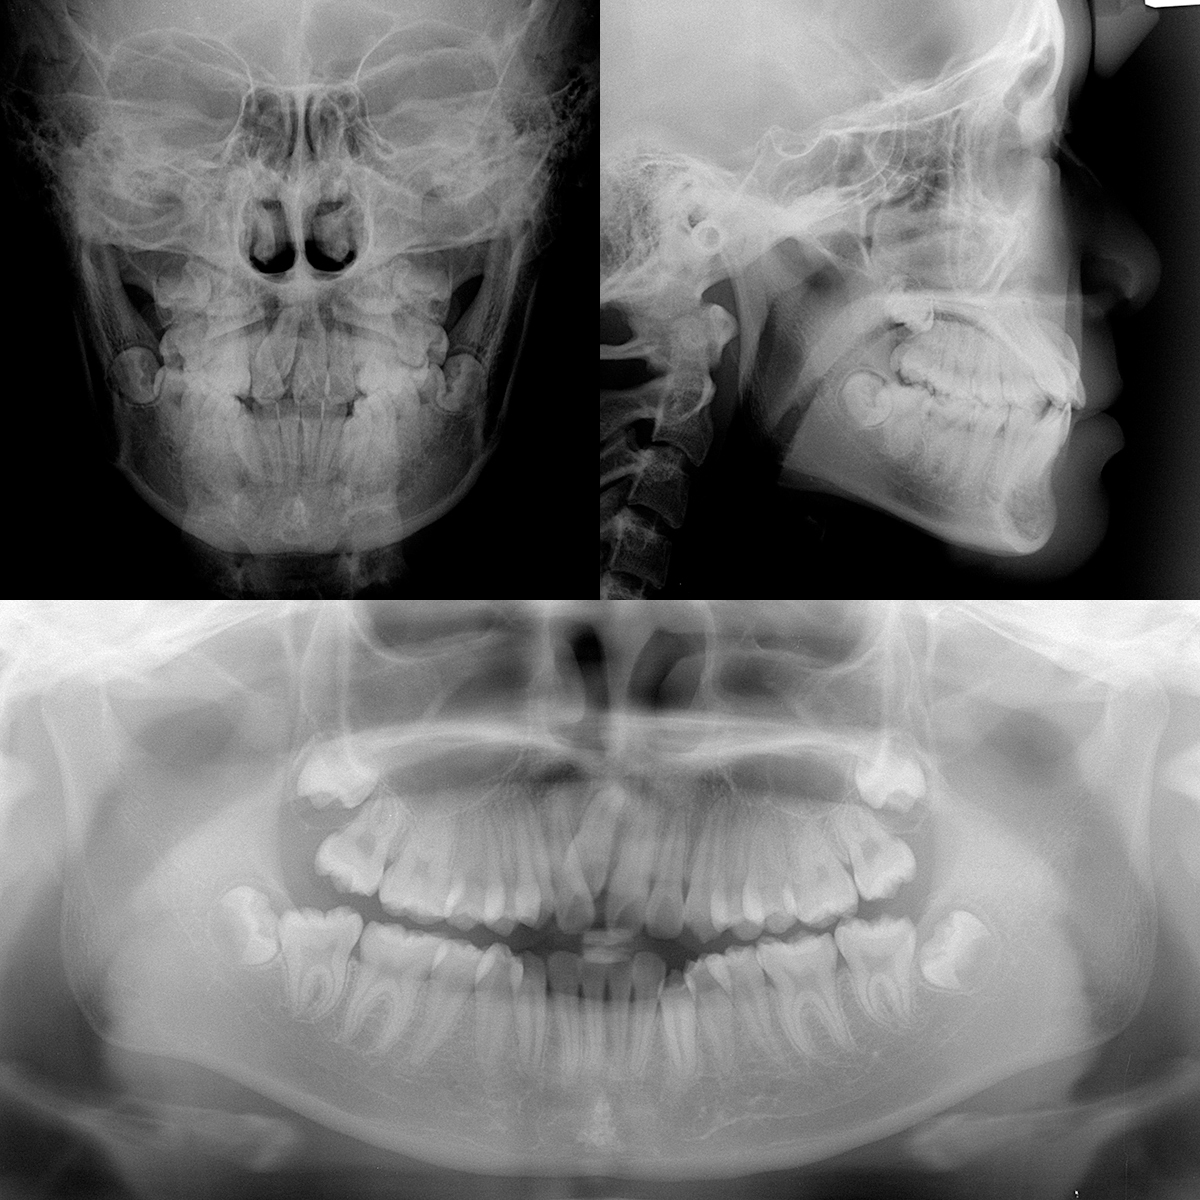

| 主訴 | 上の乳歯(上顎右側乳中切歯)が残っている |

| 初診時年齢 | 12才10か月 |

| 診断名 | 上下顎叢生を伴う上顎右側中切歯萌出遅延 |

| 抜歯or非抜歯 | 抜歯 |

| 抜歯部位 | 上顎右側:乳中切歯、第一小臼歯 |